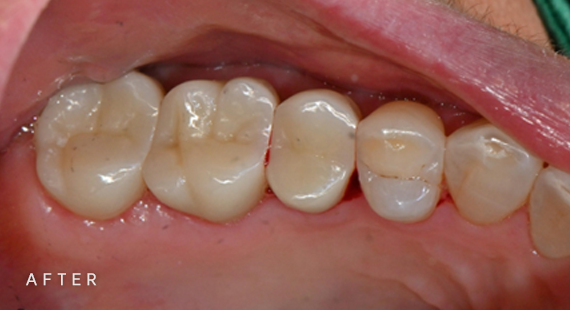

충치치료